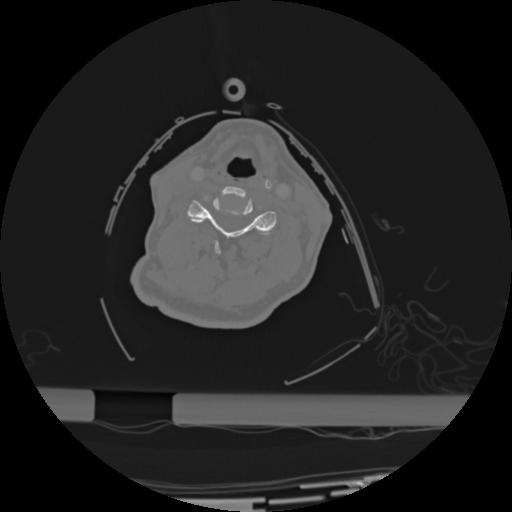

22 ANGIO,CE,Vol,0.5,ANGIO,,